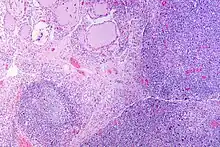

![]() | |

| A micrograph of the thyroid of someone with Hashimoto's thyroiditis | |

Microscopic examination (histology) will show diffuse parenchymal infiltration by lymphocytes including plasma B-cells.[60] The lymphocytes are predominately T-lymphocytes with a representation of both CD4 positive and CD8 positive cells.[5] The plasma cells are polyclonal, with present germinal centers resembling the structure of a lymph node[5] (aka secondary lymphoid follicles, not to be confused with the normally present colloid-filled follicles that constitute the thyroid).[60]

Atrophic colloid follicles are lined by Hürthle cells (cells with intensely eosinophilic and granular cytoplasm, which are a metaplasia of the normal cuboidal cells that line the thyroid follicles).

Fibrous tissue may be found throughout the affected thyroid as well.[5] In late stages of the disease, the thyroid may be atrophic.[10] Severe thyroid atrophy presents often with denser fibrotic bands of collagen that remains within the confines of the thyroid capsule.[60]

Generally, pathological findings of the thyroid are related to the amount of existing thyroid function - the more infiltration and fibrosis, the less likely a patient will have normal thyroid function.[5]